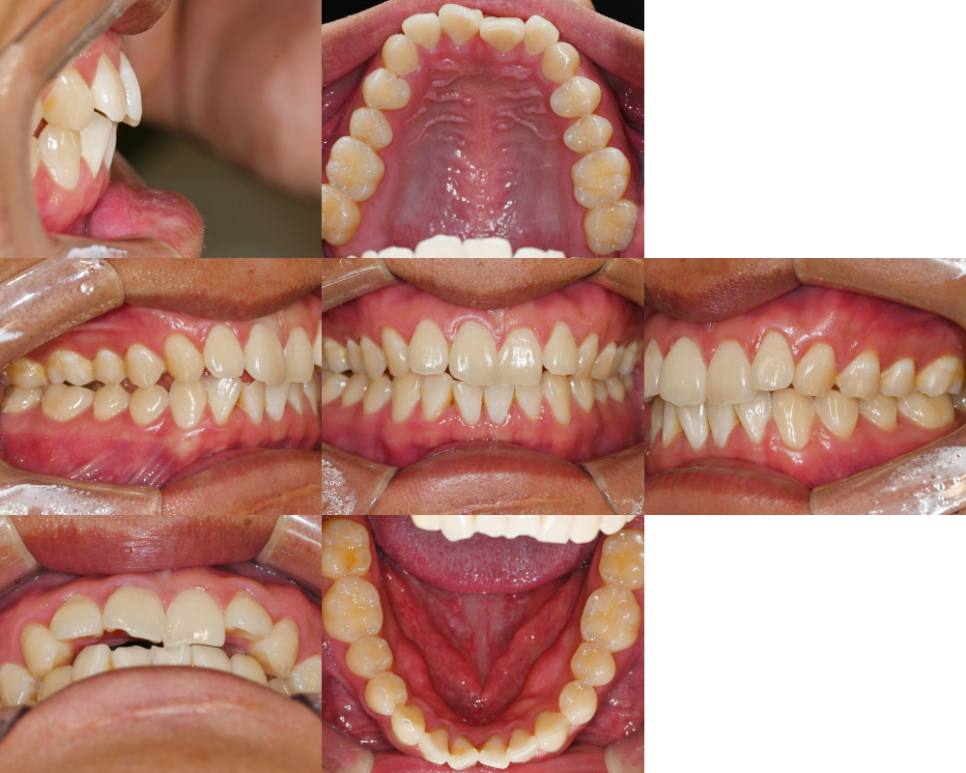

구강 내 모습을 보면

전치부에 옥니 증세가 있었습니다.

더불어, 위아래 앞니가 삐뚤빼뚤하며

위 악궁의 형태가

네모난(Square) 형태인 것을

확인할 수 있었습니다.

추가로 좌우 교합의 형태가

서로 다른 것을 알 수 있었으며,

더불어, 우측의 어금니 수평피개가

부족하여 맞물림이 원활하지 않는 것을